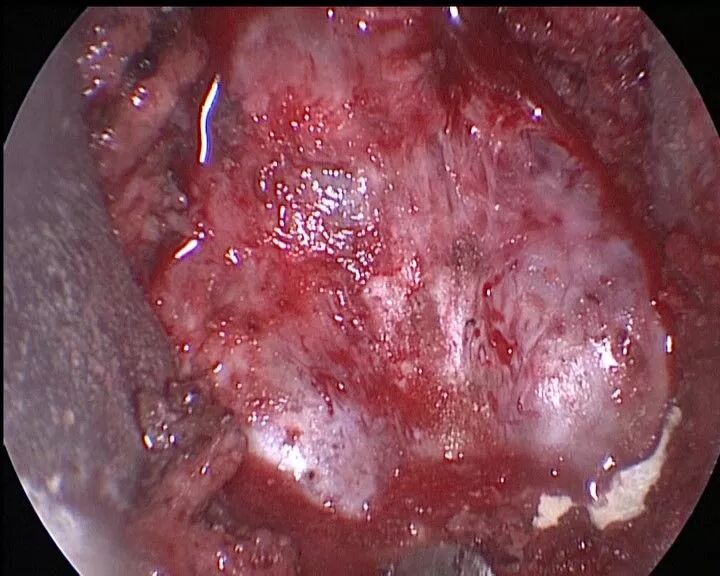

电凝并切开增厚的脉络膜

完全开放四脑室正中孔